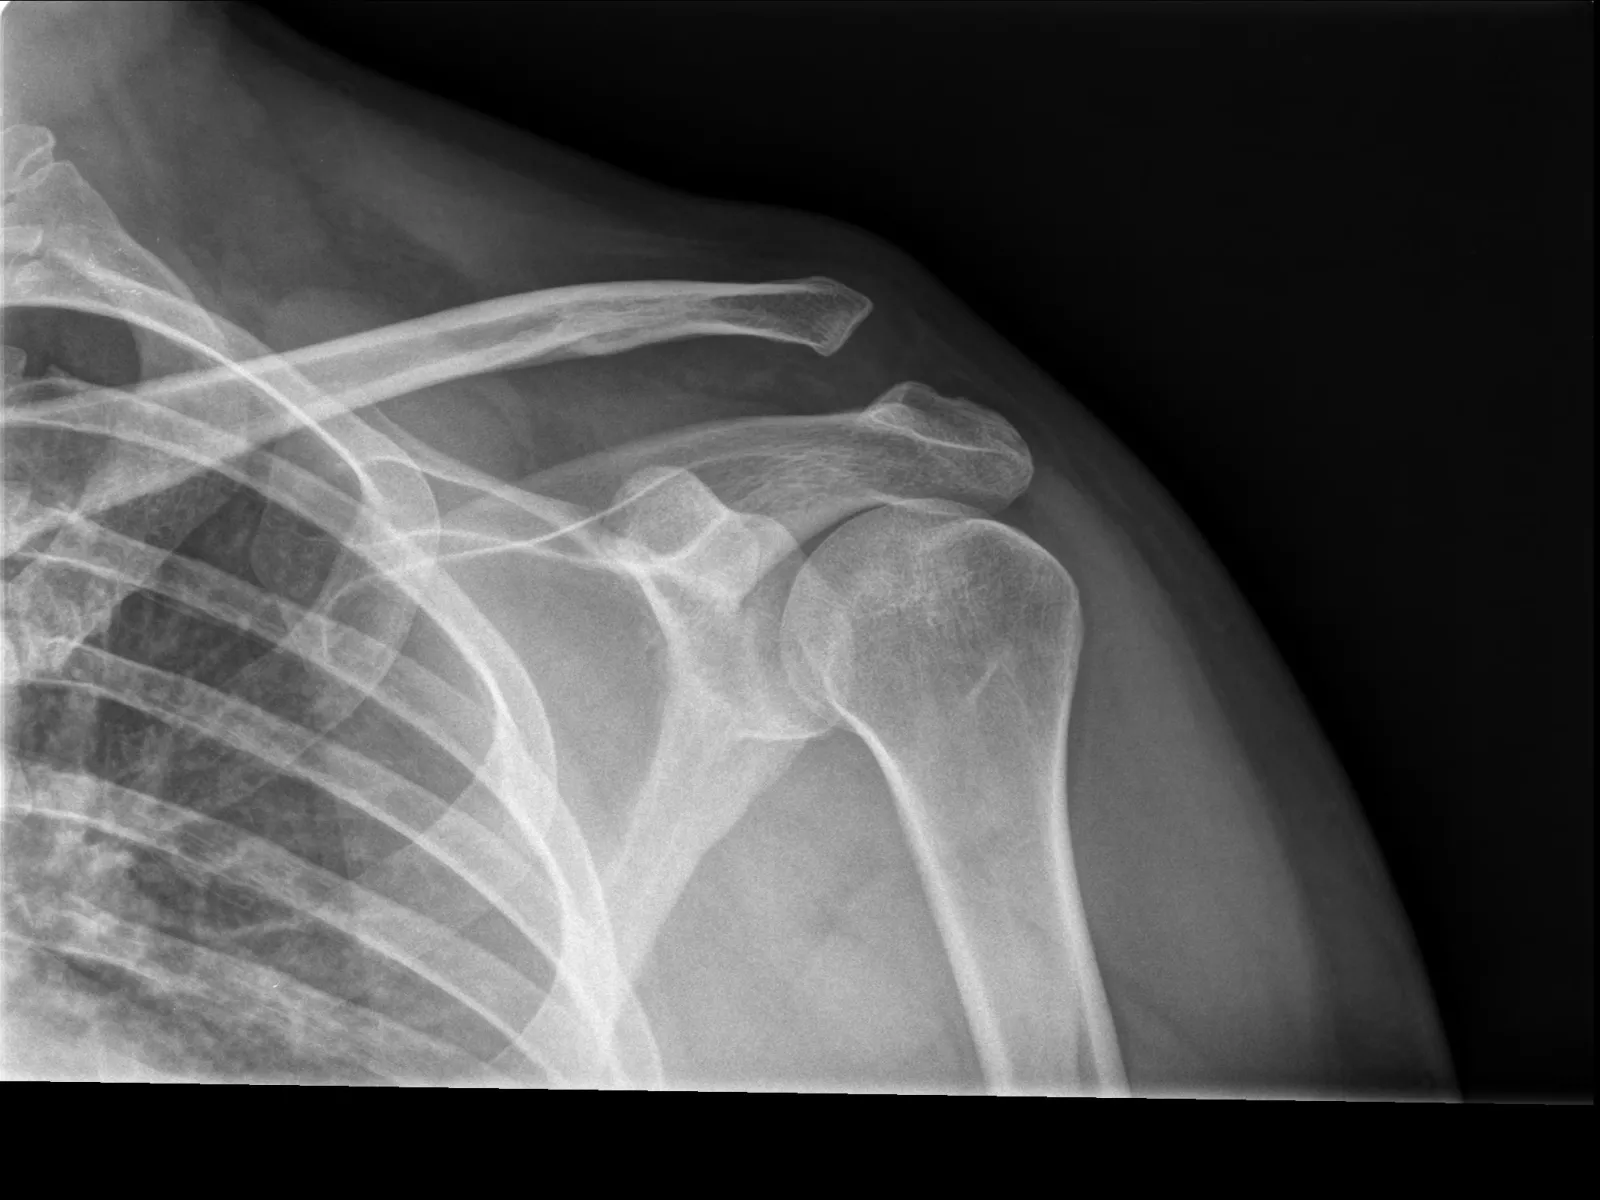

total, media hora después, con un dolor infernal, baja, le cuento y me dice que por qué no voy al médico de abajo que es mejor que el de pista, me acompaña, entramos, cuento el rollo que no tengo seguro pero pago lo que sea, ahh, eso sí, antes de que me preguntéis, no tengo la cartera, y al ver mi desesperación, me dice, ok, no pasa nada, vuelve luego y pagas, vale, me hacen rayo y finalmente tenía una luxación en el hombro, adiós temporada, adiós...